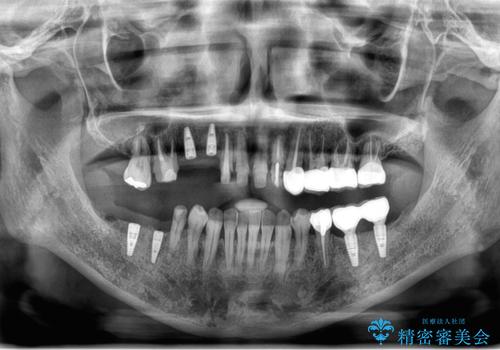

虫歯・噛み合わせ・インプラント、全顎総合治療

- 「歯の見た目が悪く、奥歯も噛みづらい、しっかりと全体的に治療したい。」と全顎的な治療を希望され来院されました。

虫歯・感染根管・予後不良歯・欠損・不正咬合、複合的な問題を一つづつ丁寧に解決し、将来に渡り不安のない口腔内環境にすべく全体的な総合治療を行っていきます。

安定する噛み合わせの位置を探りながらの治療となりました。

最終的に非常に安定した咬合関係を構築できたので、しっかりとどんな食事でも楽しめると同時に、清掃性も高く清潔な口腔内環境を確立できました。